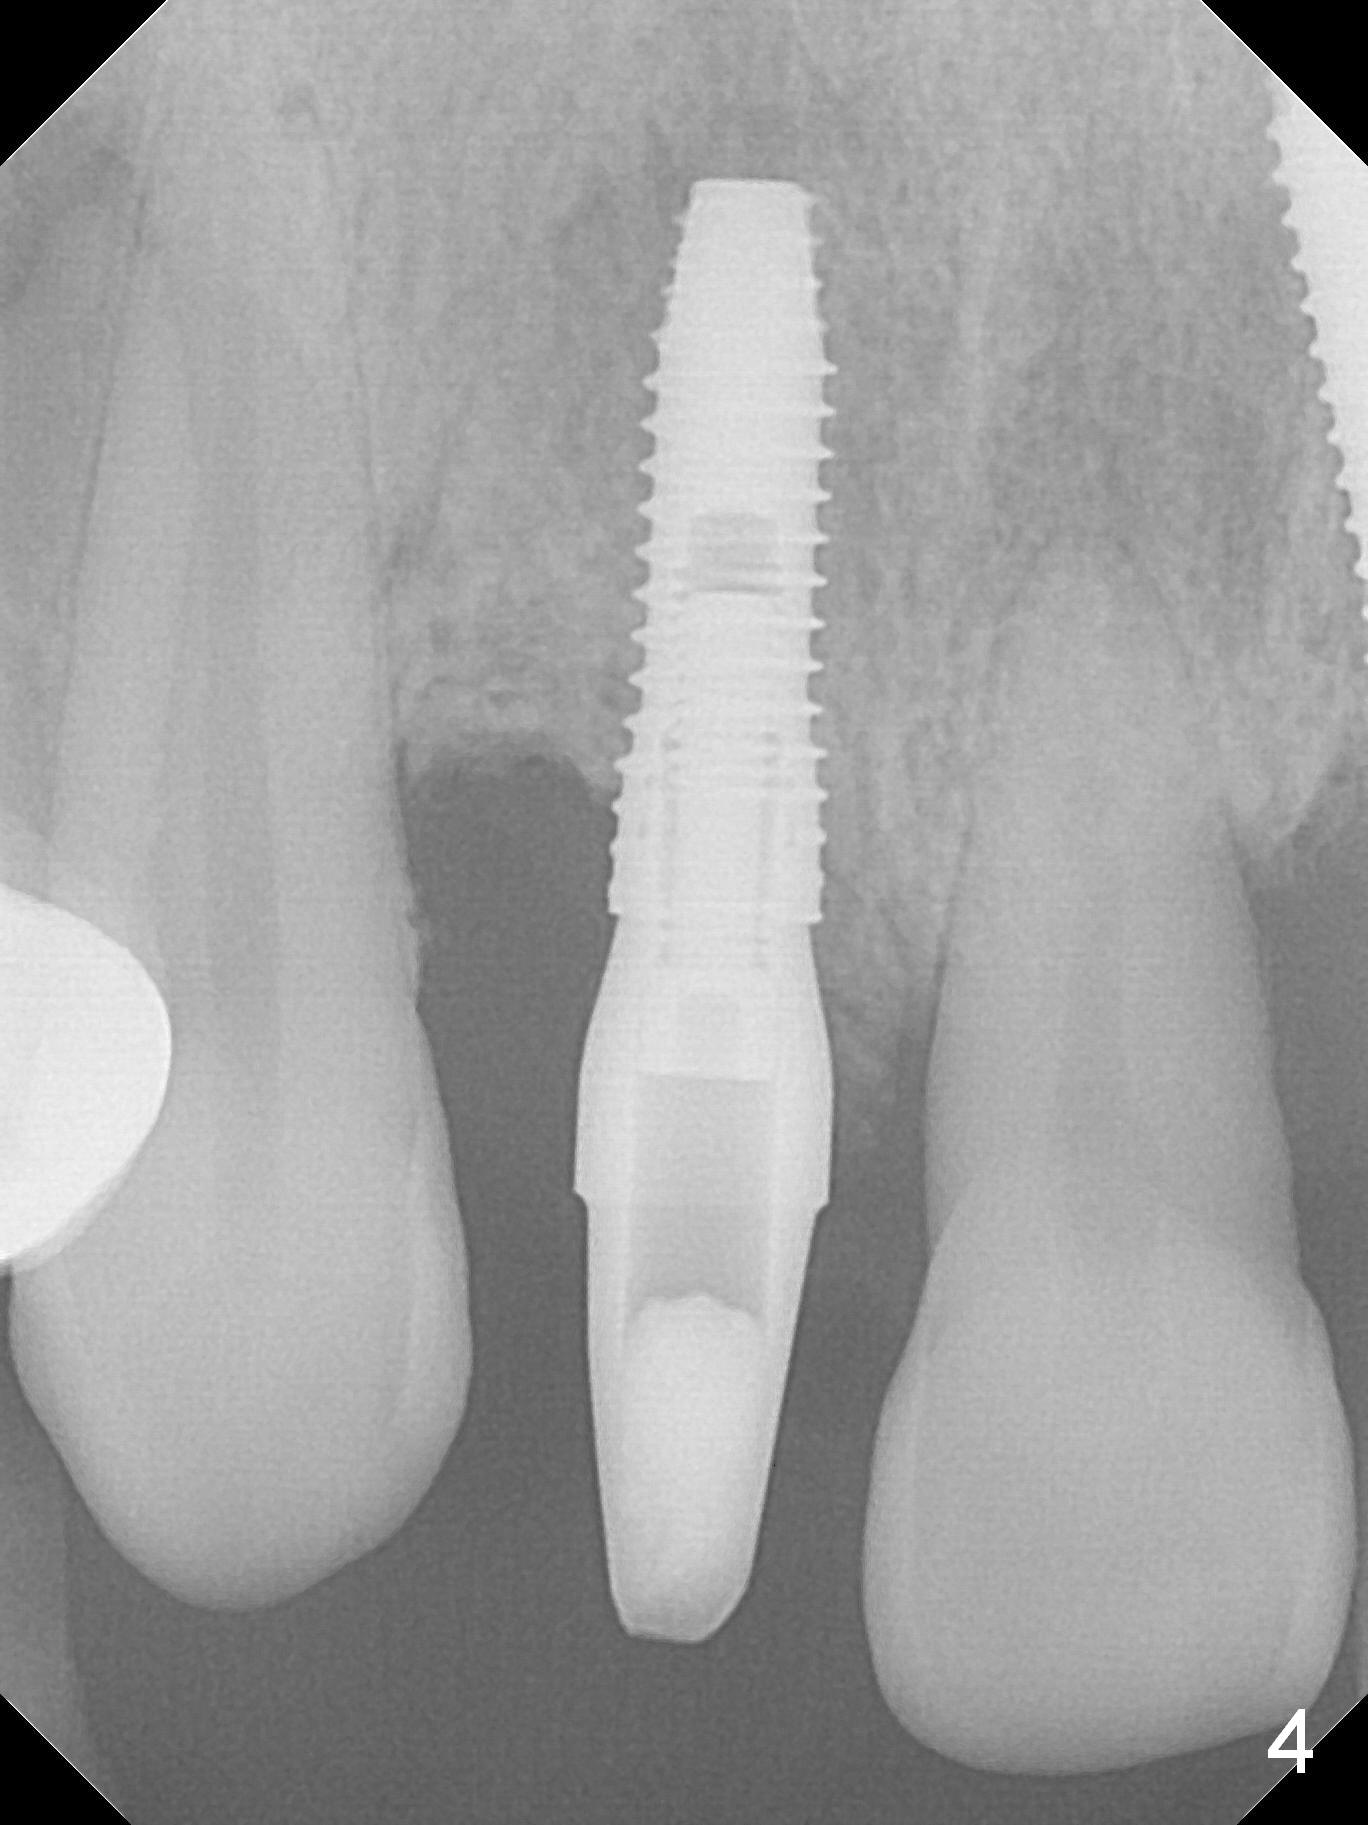

In fact the buccal plate feels to be perforated when 2 mm initial drill is being used probably at the deepest area of the concavity shown in Fig.2 (near B). The trajectory is adjusted and the osteotomy is enlarged by 3 mm drill for 13 mm (Fig.3). When a 3.8x13 mm implant is placed (50 Ncm), an angled abutment is used (Fig.4, 4.5x15°(A)5 mm). As planned, a 3.8x13 mm implant is placed at #13, while bone graft is placed mesial and palatal to #15 implant. No provisional is fabricated from #9 to 15 due to time limitation and lack of parallism between the abutments.